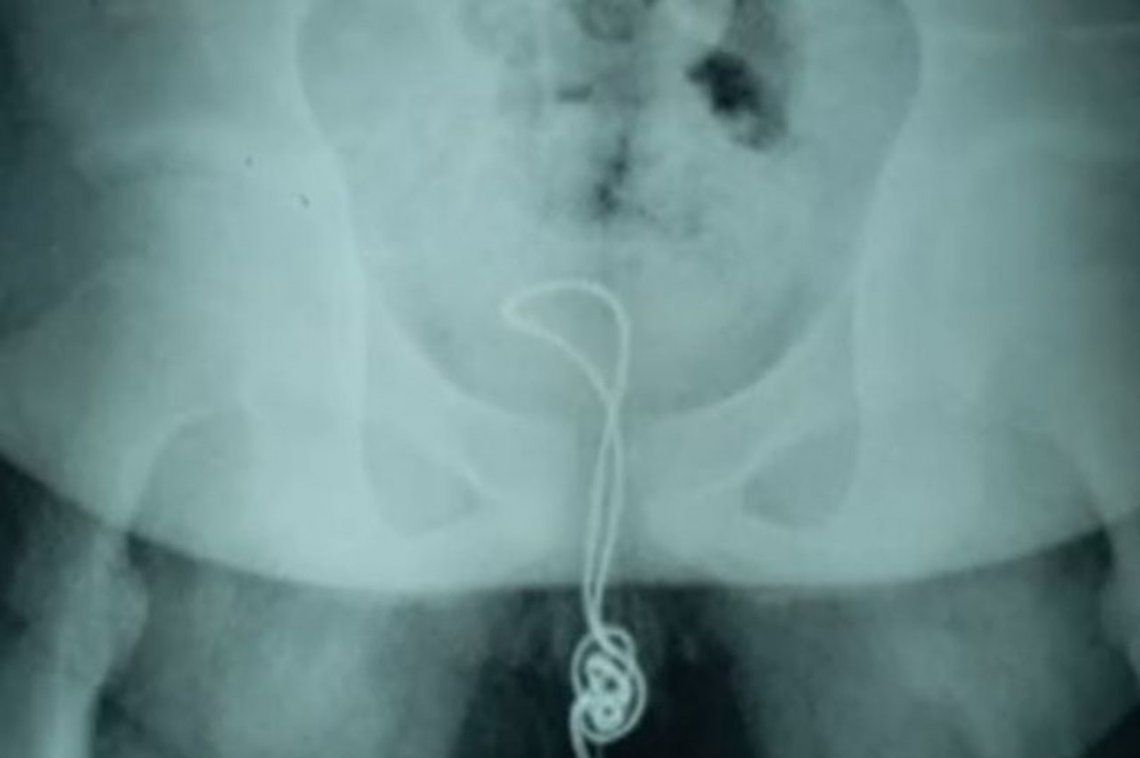

Un adolescente debió recibir una cirugía de urgencia para removerle un cable USB que se encontraba enredado en su vejiga, según reveló el periódico inglés Mirror.

El joven de 13 años y oriundo de Linkou, China, se introdujo alrededor de 20 centímetros del objeto por su uretra, pero luego comprobó que no podía removerlo y debió solicitar ayuda a sus padres, quienes lo trasladaron hacia el hospital.

"El cable llegó a su vejiga, donde se enredó y terminó en un nudo, por lo que cuando trató de sacarlo, se quedó atascado", sentenció el profesional.